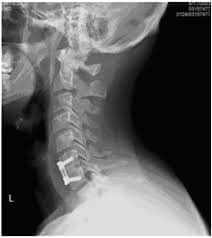

Cervical disc replacement surgery, also known as cervical disc arthroplasty, is a procedure in which a damaged cervical intervertebrael disc is removed and replaced with a mechanical artificial disc. These devices are typically made from titanium combined with other materials.

Although the artificial disc may lack some of the absorptive qualities of a biological disc, it allows for natural motion at the spinal segment between two vertebraee. Examples of artificial cervical discs include: